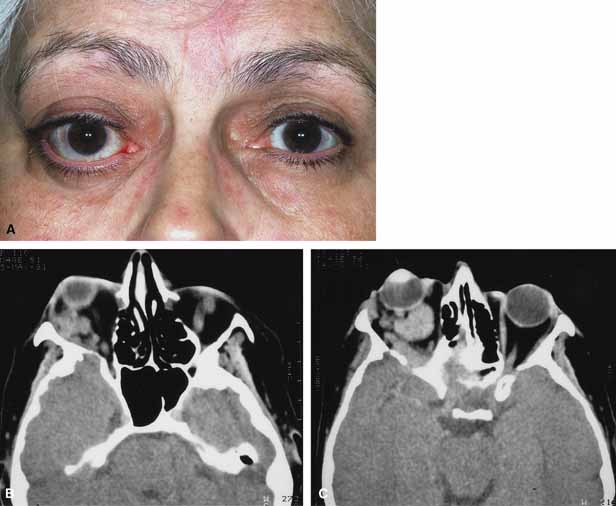

Venous flow malformations (so-called varices) generally refer to those vascular malformations with weakened segments of the orbital venous system, of variable length and complexity.76,77 They may appear as superficial, deep, or combined lesions and may be of a distensible or nondistensible variety. Because they are intrinsic to the systemic circulation, distensible primary varices enlarge with increased venous pressure, and their distensibility varies with the residual thickness and strength of their wall. The lesions often cause intermittent proptosis, pain, and/or bruising because of expansion brought about by physical effort (straining, Valsalva maneuver) or bending (Fig. 10A, 10B and 10C).78 Sudden proptosis may result from hemorrhage into one of the varices or the creation of a one-way valve effect trapping blood within the lesion. High-dose steroids, canthotomy, and cantholysis may be of benefit to decrease the orbital pressure. Direct surgical excision is difficult because of the tortuous tangles of fragile, thin-walled malformed vessels and their tendency to rupture and bleed excessively.59 Nondistensible varices may also appear as superficial, deep, or combined lesions. Clinically they are similar to lymphangiomas and characterized by episodes of acute exacerbation and remission related to hemorrhage or thrombosis within the lesion. Hemorrhage into deeper lesions causes sudden proptosis, pain, decreased motility, and reduced vision. Profound orbital hemorrhage with visual deterioration and pain is treated in a manner similar to that of lymphangioma and orbital hemorrhage (canthotomy, cantholysis, and/or orbital exploration with evacuation of clotted blood and excision of the associated lesion).

Fig. 10 A. A 68-year-old female presented with intermittant proptosis occurring on bending over. B. Multiple, oval shaped, contrast-enhancing masses are present in the right orbit. The masses enlarged with valsalva and were consistant with a diagnosis of orbital varix. C. Multiple, oval shaped, contrast-enhancing masses are present in the right orbit. The masses enlarged with valsalva and were consistant with a diagnosis of orbital varix.